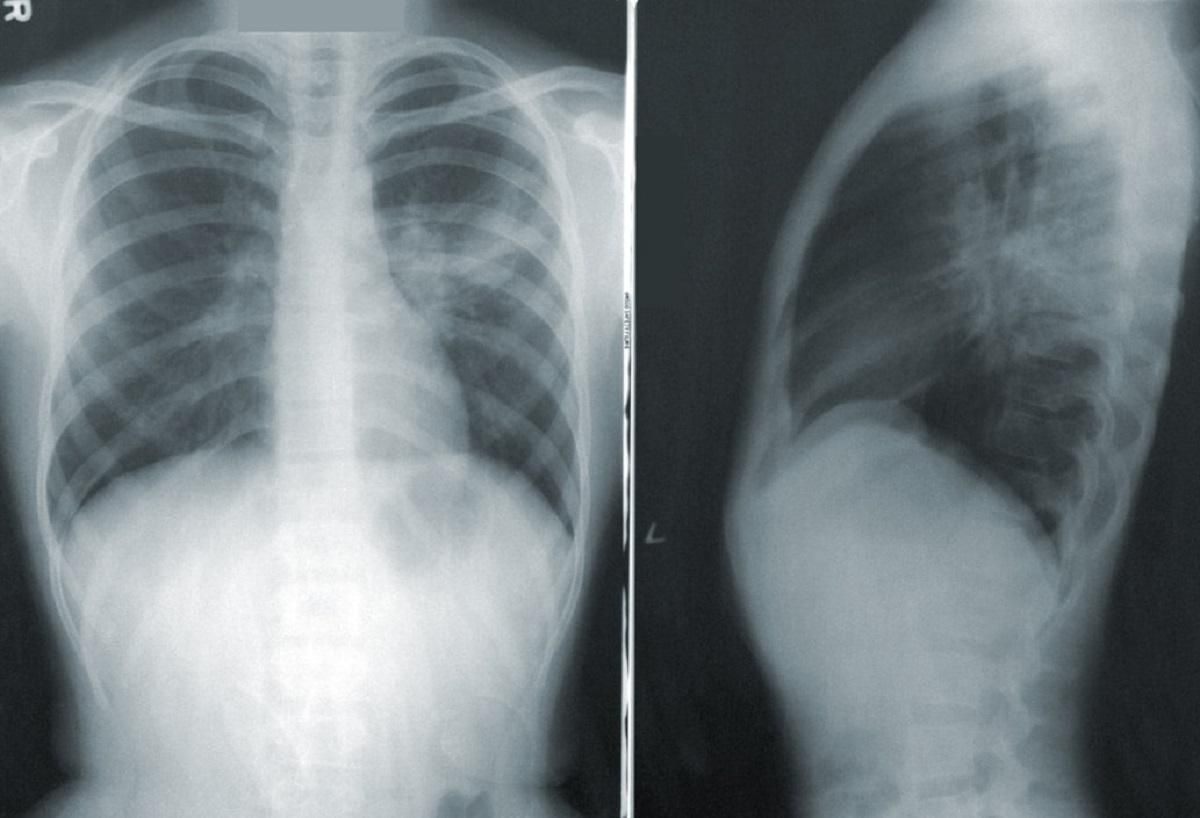

Также КТ назначают, ввиду тяжелого состояния пациента (даже если ПЦР-тест показывает отрицательный результат). В Минздраве объяснили, как получить и воспользоваться направлением на бесплатную компьютерную томографию.

Решение о выдаче или невыдаче направления должен принимать врач, опираясь на общее состояние пациента, наличие дыхательной недостаточности, показатель сатурации (насыщенности крови кислородом) и температуру тела.